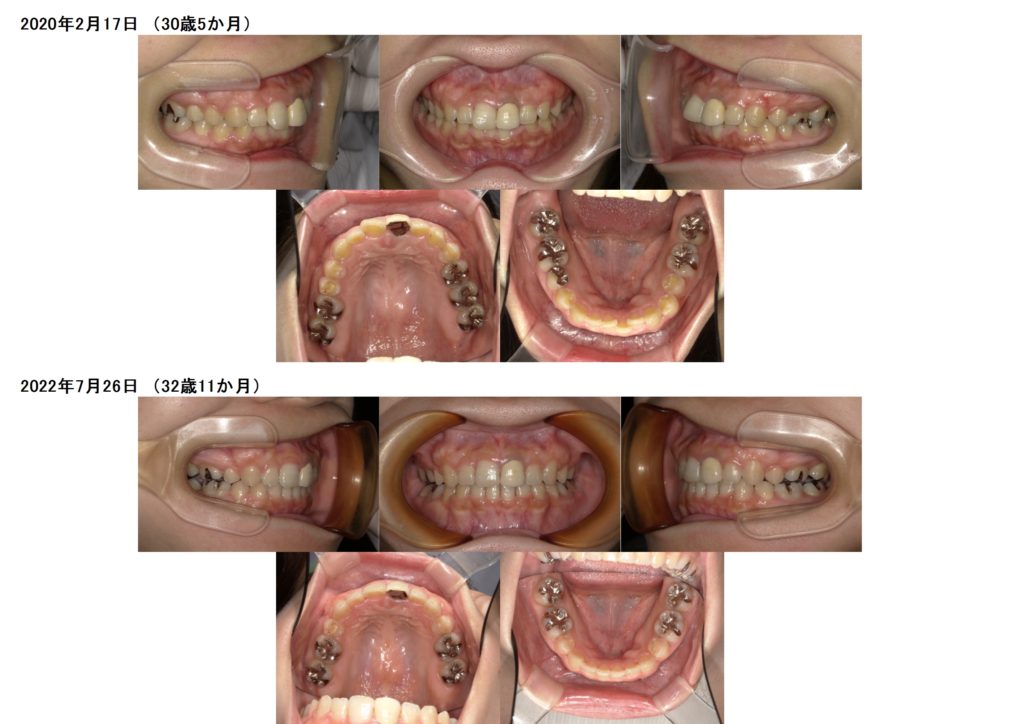

治療前、治療後の口腔内の写真になります。

お口元も随分と変わりましたよっ☆

生まれつき永久歯がない方(先天性欠如)や、乳歯が残っている方、永久歯が埋まっている方(埋伏歯)でも、ブラケットの治療、マウスピースの治療ももちろん可能です!!